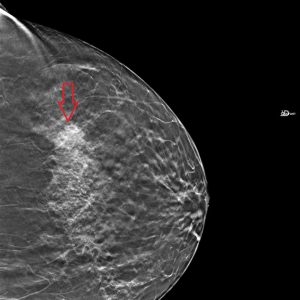

Best views of the ‘questionable distortion’ mentioned on report

- Architectural Distortion L MLO Breast Tomosynthesis

- Architectural Distortion L CC Breast Tomosynthesis